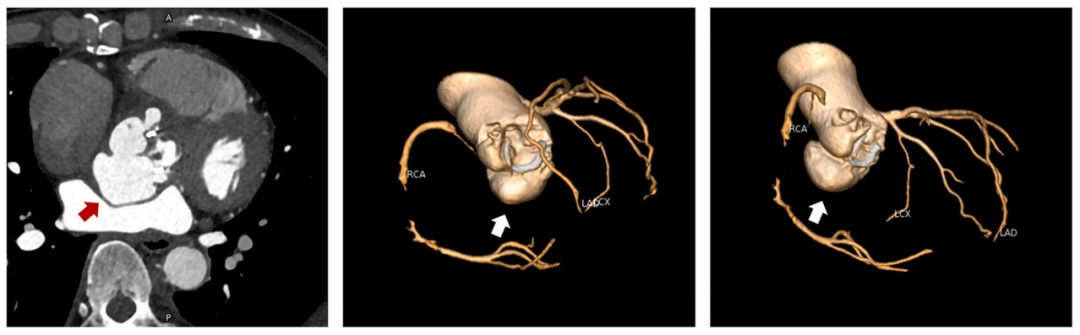

冠脉CT显示右冠窦瓣周脓肿(图2A)伴右冠窦至右心房瘘管形成(图2B)。右冠窦及无冠窦下方有大量脓肿,压迫左心房并侵蚀右纤维三角(图3)。由于赘生物侵袭导致右冠状动脉(RCA)近段慢性闭塞,右冠状动脉中段观察到栓塞碎片(图4)。患者高敏肌钙蛋白(hs-cTn)升高至2090ng/mL符合冠脉栓塞引发的心肌损伤表现,以上共同表明为IE导致的广泛解剖破坏,涉及瓣膜及瓣周结构。

图3